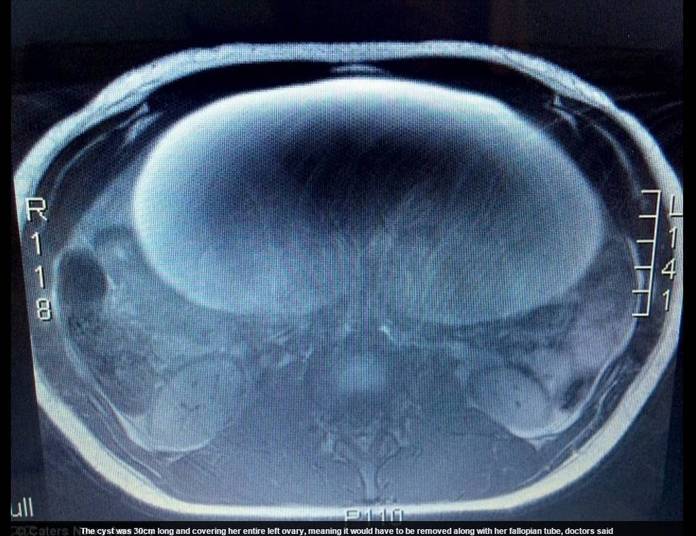

A primeira vez que Olivia percebeu algo de diferente em seu corpo foi

durante as férias de 2013. Mas foi só em novembro de 2014 que ela começou de

fato a sentir dores, e que sua barriga dobrou de tamanho. Exames mostraram o

cisto de 30 cm, e um tumor em seu interior — ambos já tinham “engolido” o

ovário de Olivia, além de sua trompa. Com isso, ambos precisariam ser removidos

em uma cirurgia.